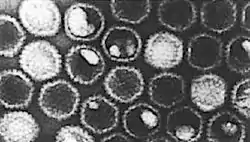

Gallid herpesvirus 1 (GaHV-1) (también conocido como Herpesvirus 1 aviar) es un virus de la familia Herpesviridae que causa la laringotraqueitis infecciosa aviar. Se reconoció originalmente como una enfermedad de las gallinas en Estados Unidos en 1926.[1] La enfermedad también ocurre en faisanes.[2] GaHV-1 es esparcido con las secreciones respiratorias y transmitido por la inhalación de gotitas. Una bandada de aves no expuesta previamente desarrollará casos durante dos a ocho semanas luego de la introducción. El periodo de incubación es de dos a ocho días.[1] Los síntomas incluyen tos, estornudo, sacudidas de cabeza, letargo, secreciones de los ojos y las fosas nasales (a veces sanguinolentos), y dificultad respiratoria. El nombre viene de la inflamación severa de la laringe y la tráquea. Puede formarse una membrana diftéritica en la tráquea, que causa obstrucción. La mortalidad es típicamente menor del 15 %.[2] Existe una vacuna disponible, pero no previene las infecciones latentes.